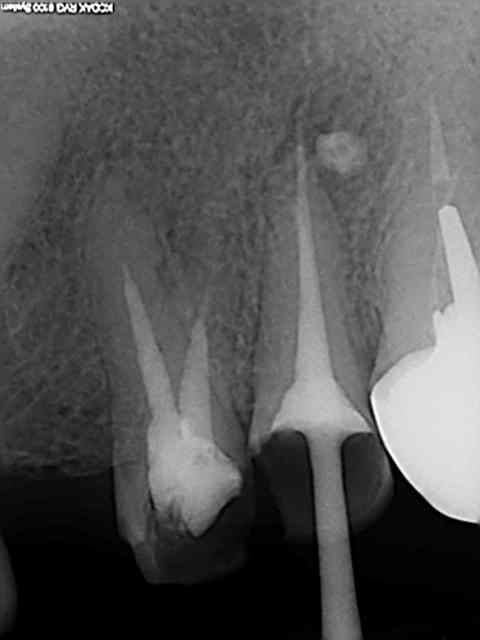

Ce sont des cones dentsply mais pas les réciprocs. je les scelle au tubuli seal en pompant un peu ( d'ailleurs sur la 25 ci dessous qui avait un 4eme ca a fait un dépassement preuve que ca fuse) je les coupe ensuite au système B avec le pluggeur qui sert à faire le bouchon apical.

Tres pratique d'ailleurs pour faire le cas échéant les tenons dans la séance de l'endo, l'empreinte et la provisoire dans la foulée.

Tu as fait des progrès. Disons par exemple que sur la deuxième prémolaire, tu es allé un poil trop loin, ce qui a réduit sérieusement la constriction apicale. Peut être que que tu mesures ta LT un demi millimètre plus longue que nécessaire.